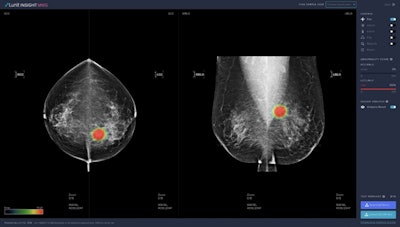

Lunit's AI algorithm generates a numerical score that represents the likelihood of a particular mammogram showing cancer. Higher scores from the software equate to greater suspicion of cancer.

Lunit Insight MMG showed similar strength in the JAMA Oncology study, which compared the performance of radiologists and three different AI programs for detecting cancer from more than 8,000 mammograms.

The Lunit program achieved a sensitivity of 81.9%, higher than the other two programs evaluated in the study as well as first-reader radiologists (77.4%) and second-reader radiologists (80.1%).